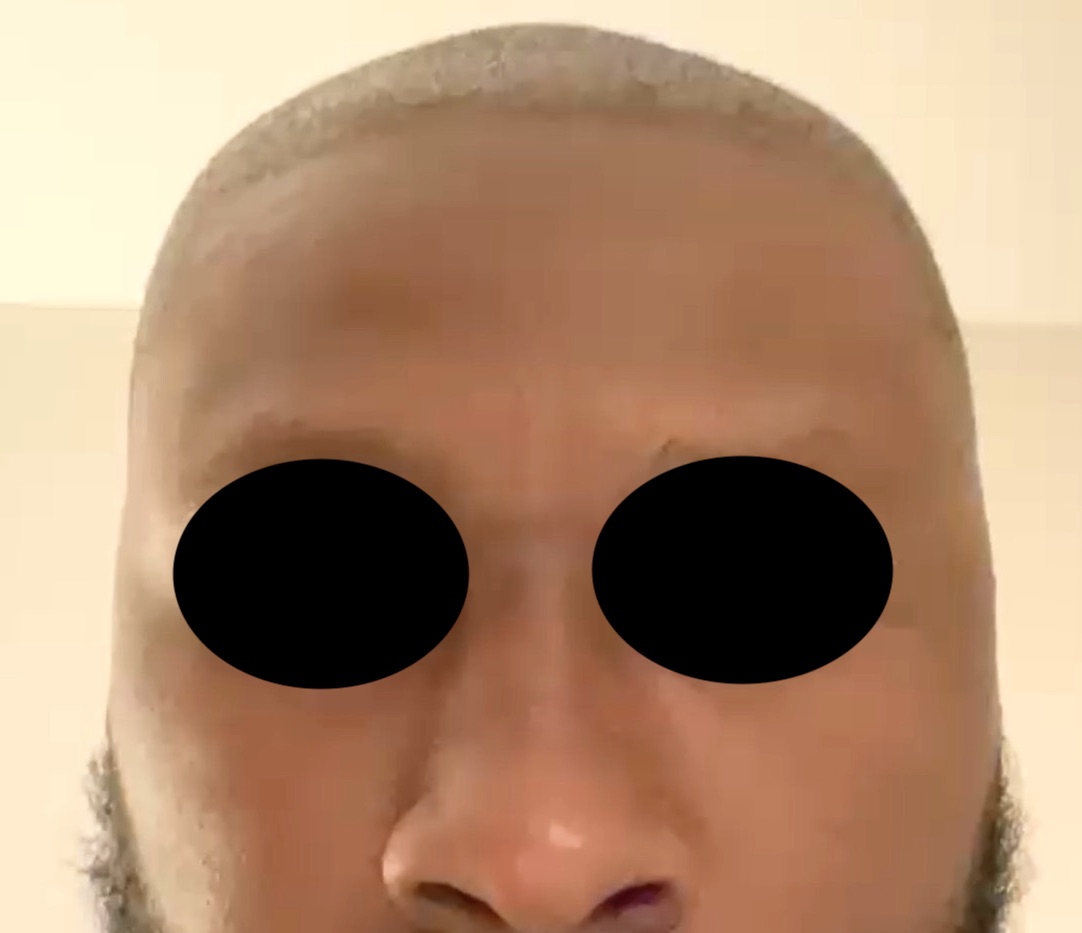

Patient 100

Desire for reshaping of an asymmetric flat back of the head in a shaved head male.

A combined back of the head reshaping procedure was done with a custom skull implant, sagittal ridge reduction and a right temporal muscle reduction.

Desire for reshaping of an asymmetric flat back of the head in a shaved head male.

A combined back of the head reshaping procedure was done with a custom skull implant, sagittal ridge reduction and a right temporal muscle reduction.